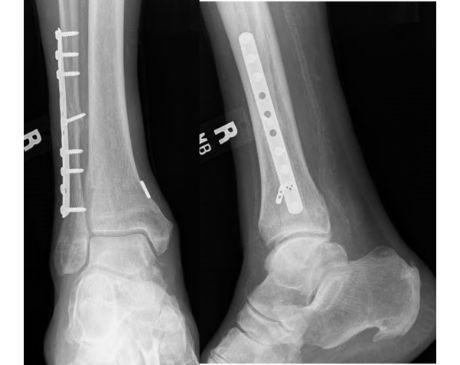

I was hit by car, had a compound fracture with a bone sticking out of my left foot. Broken tibia and fibia?. Screwed plate and bones back together. I am healing fine, next visit 3/26 to remove stiches. I seem to have total function of foot. Still have 2 more weeks of not using leg, but very hopeful.